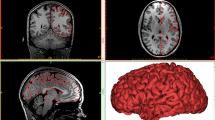

T1W MRI images in sagittal (a), coronal (b), and axial (c) planes with images of the corresponding 3D printed model in different views (d–f). This is a 10-year 6-month-old girl who suffered a remote prior hypoxic ischemic injury at term, with a combined partial prolonged and profound injury. The corpus callosum is diffusely thinned as a result of global atrophy (white arrows in (a)). The green arrows depict areas of focal cystic encephalomalacia and ulegyria within the anterior inter-arterial watershed of both cerebral hemispheres and the corresponding overlying cortical atrophy. The blue chevron depicts an area that required a manual patch (after automatic segmentation) to cover a defect due to the segmentation not recognizing the residual thin cortex overlying the cystic encephalomalacia. The red arrows depict atrophy with deep sulci of the posterior inter-arterial watershed bilateral. The asterisks (white and black) depict inter-hemispheric fissure widening due to the diffuse atrophy and associated lentiform separation of the hemispheres at the involved regions

The advantage of obtaining 3D printed models to provide a global view of pathology and show the effect of diffuse atrophy on the brain volume is clear, as shown in Fig. 8. This is especially striking when someone is given the model to handle. In addition, when a pathologic model is placed alongside an age-matched normal model, the differences in size are immediately and easily apparent (Fig. 8). An additional advantage is the ability to view both sides simultaneously from different vantage points, and hence appreciate bilateral and symmetric disease, which defines a global injury such as the cortical changes from partial prolonged HII. Confidence in the maintenance of fidelity of linear measurements is paramount for medical practice and communicating medical findings as well as in medical litigation.

Two models of different children’s brains side by side for comparison. Both patients suffered partial prolonged hypoxic ischemic injury at term gestation, now with cerebral palsy, who had delayed MR imaging — a 2-year 2-month-old boy (a) and a 11-year 6-month-old boy (b). Note, the more severe atrophy in the 11-year-old (b) evident from increased depth and width of the sulci in the watershed region (red arrows in each model) as well as the low overall brain volume (i.e., an 11-year-old with a similar or smaller brain volume than a 2-year-old) when visualizing the models side by side